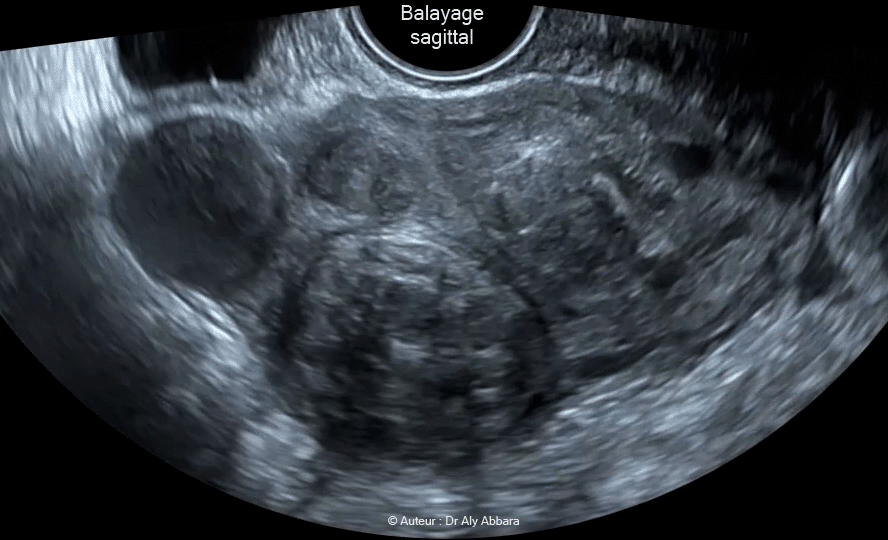

Images échographiques animées et séquences vidéos montrant un volumineux utérus polymyomateux mesurant 96 mm de largeur, 86 mm de longueur 85 mm d'épaisseur ; il comporte 9 myomes de classes différentes de FIGO : classe 1, classe 4 , classe 5 et et classe 6.

Le plus volumineux myome est intra-mural, de classe 4 et mesurant 28 x 31 x 35 mm, soit 16 cm3 de volume ; il est situé au niveau de la corne gauche de l'utérus.

Le plus petit un myome utérin est sous-muqueux (endocavitaire), de classe "1" de la classification FIGO 2011 ;

il mesure 18 x 18 x 20 mm, soit 3,7 cm3 et se développant au niveau du bord latéral droit de la cavité utérine avec une partie de < de 50 % de son volume total située dans le myomètre.

Patiente est âgée de 38 ans, mère d'un enfant de 6 ans. Elle souffrait récemment d'importants phénomènes douleurs spontanés et provoqués localisés au niveau de la corne gauche de l'utérus ; ils sont liés à une nécrobiose aseptique de plus volumineux myome décrit précédemment.